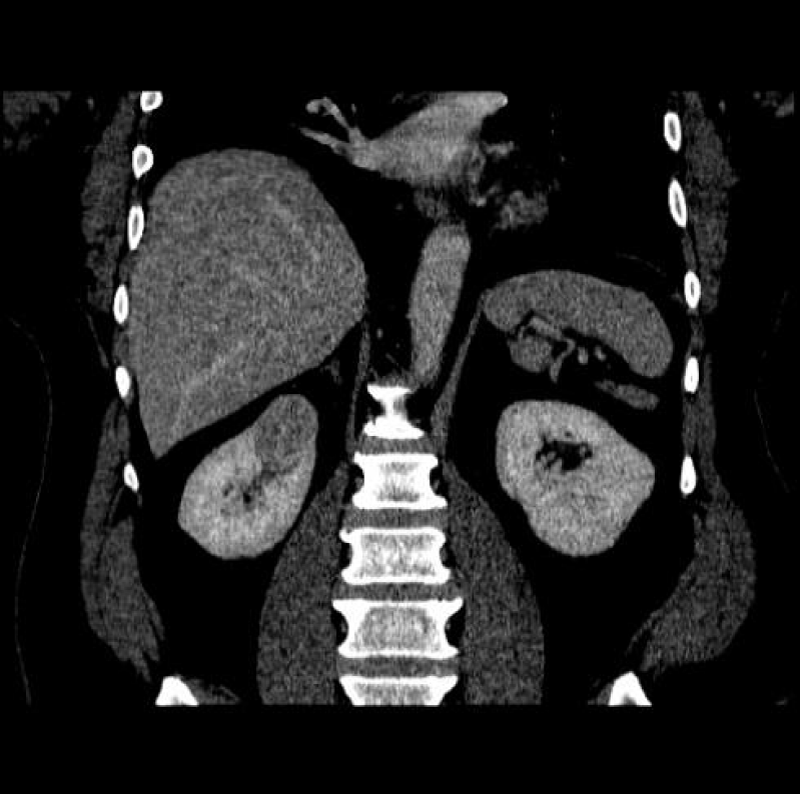

For evaluating SRM (Figure 3), thin CT slices of 2 mm to 3 mm are preferred to demonstrate lesion extent, hence minimizing ‘partial volume artifacts.’ This allows in both the coronal and sagittal planes, post-processing high-resolution Three-Dimensional multiplanar reconstructions (MPR). Maximum intensity projection (MIP) imaging processing tool projects the voxels of the highest attenuation into a Two-Dimensional image. This is especially useful post-operatively, where cortical profiles and the integrity of blood vessels may be evaluated [1,6].

Figure 3: Right renal mass measuring 2 cm.

The Bosniak classification system of renal cystic masses utilizes the contrast-enhanced CT depiction of cysts to predict the risk of malignancy. These lesions are then categorized into five groups i.e. either benign (type I and II), likely benign (type IIF), or likely malignant (type III and IV). Simple cyst features distinguishing cysts from tumors or abscesses on the US constitute, round sharp smooth walls, ‘anechoic’ absent echoes in the cyst, (Figures 10 a,b) and a strong posterior wall echo, indicating adequate transmission. When these three criteria are not satisfied, CT is indicated [1-3,5,28-30].

Figure 10a,b: Right cystic mass now with solid components concerning renal neoplasm with increased vascularity.